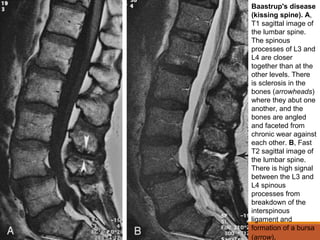

Baastrup's disease

(kissing spine). A,

T1 sagittal image of

the lumbar spine.

The spinous

processes of L3 and

L4 are closer

together than at the

other levels. There

is sclerosis in the

bones (arrowheads)

where they abut one

another, and the

bones are angled

and faceted from

chronic wear against

each other. B, Fast

T2 sagittal image of

There is high signal

between the L3 and

L4 spinous

processes from

breakdown of the

interspinous

ligament and

formation of a bursa

(arrow).